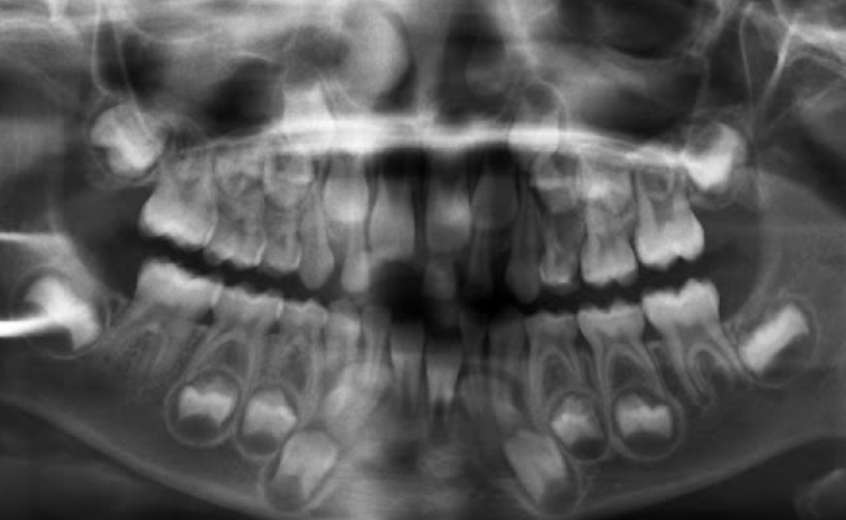

Permanent lower incisors present? Yes, so definitely 6-7

Permanent upper Incisors not erupted yet. Therefore not 7-8 y.o.

Conclusion = 6 y.o